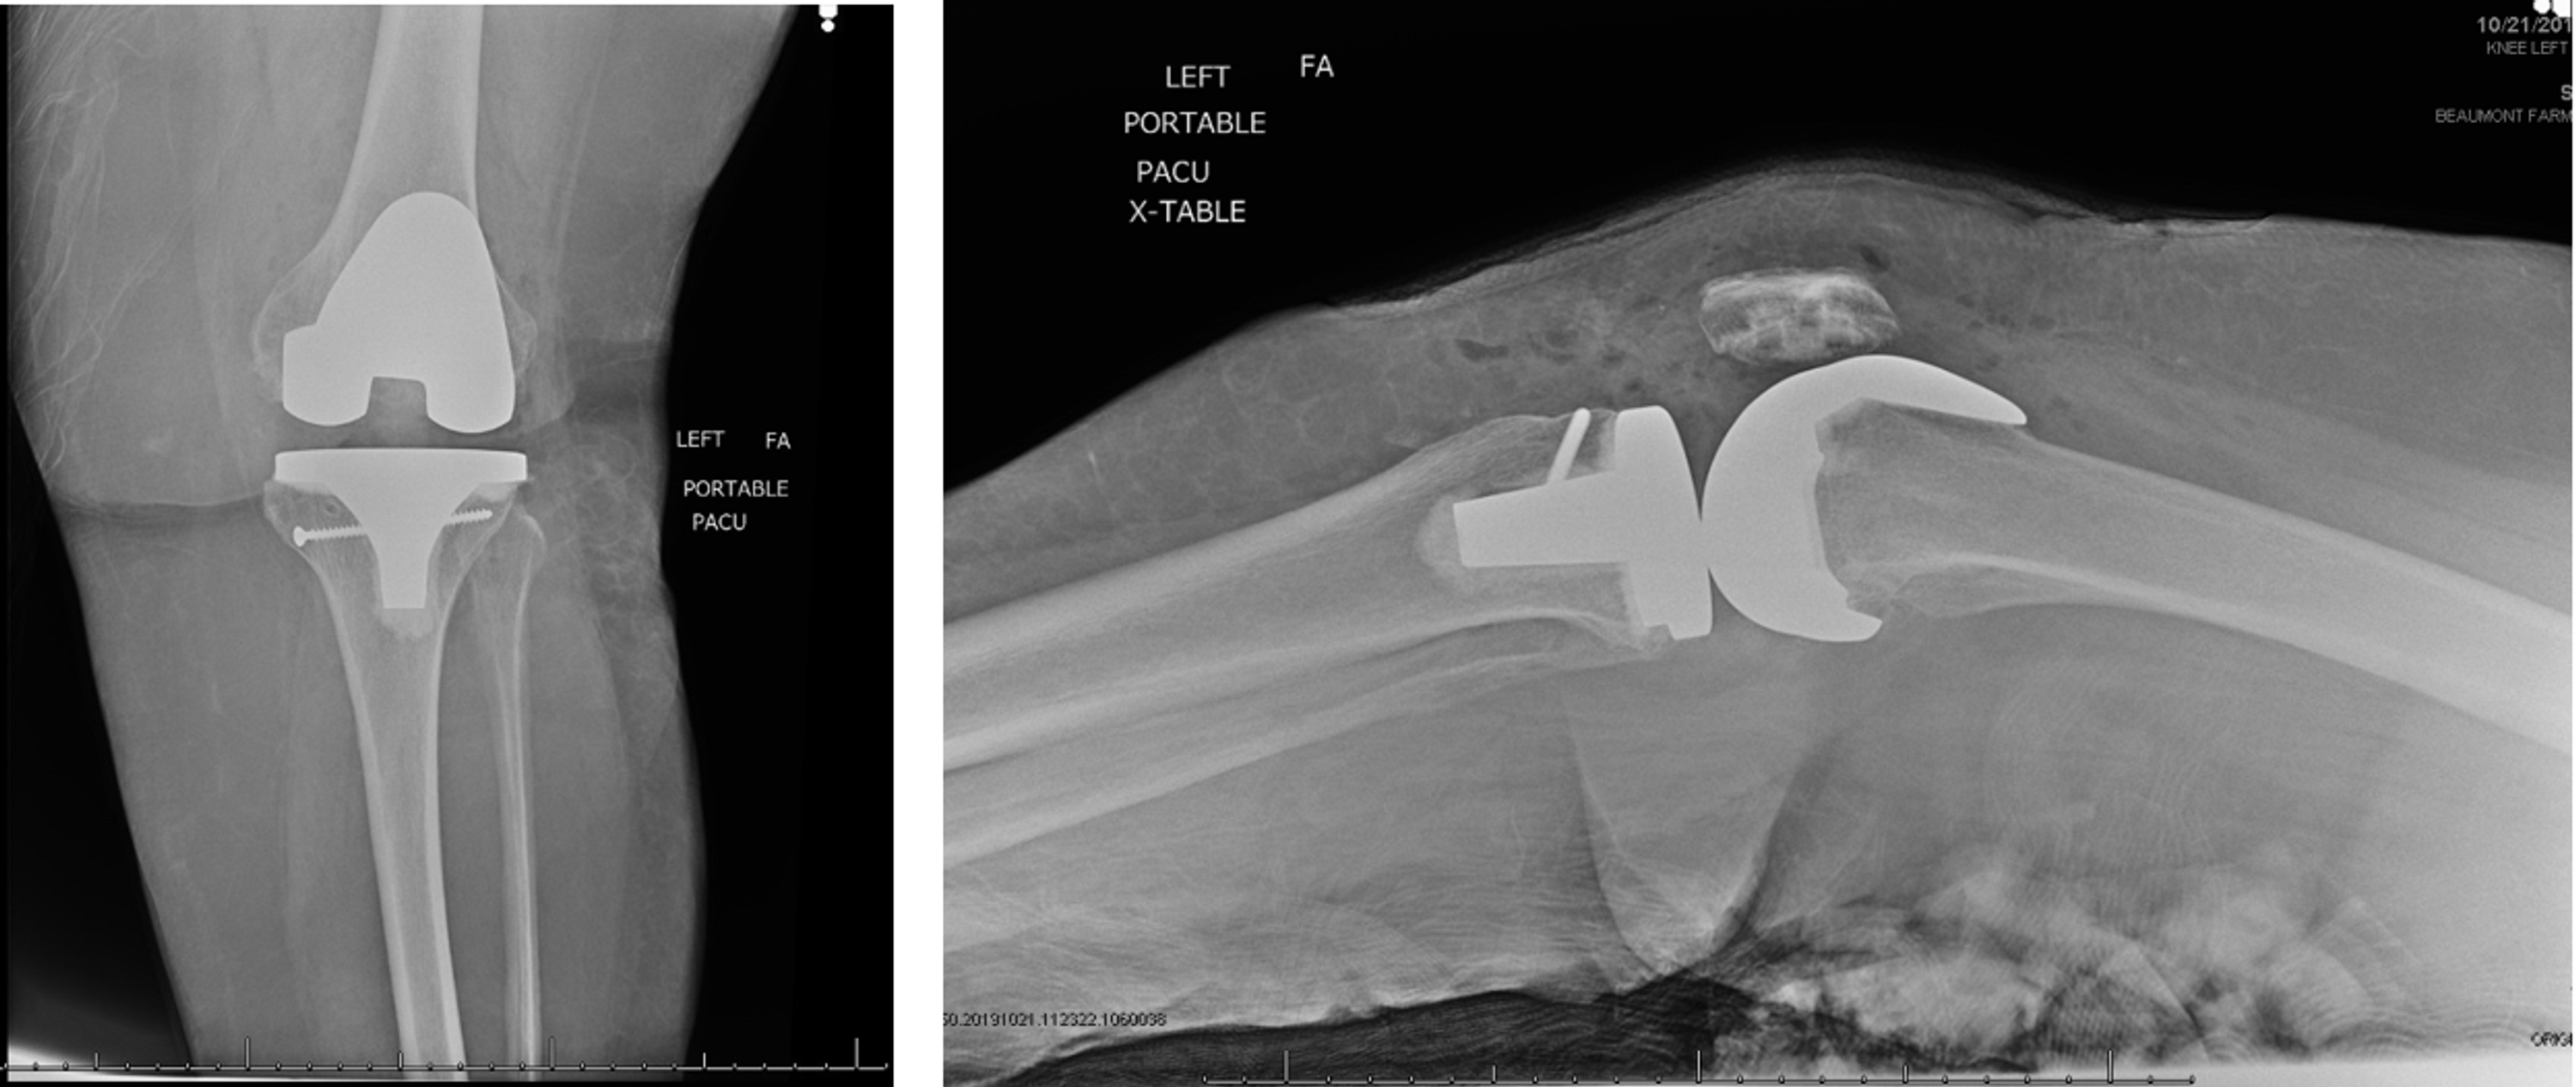

Cureus Intraoperative Tibia Fractures During Primary Total Knee Pain In Knee Tibia Fracture Here we explain the various types and causes, as well as treatment and rehabilitation. — a tibia fracture in the lower leg is the most common injury of all long bone fractures. A fracture is another word. Tibia and fibula fractures are two broken bones in your lower leg. Symptoms include pain, an inability to walk, a popping sound. Pain In Knee Tibia Fracture.

Cureus Intraoperative Tibia Fractures During Primary Total Knee Pain In Knee Tibia Fracture Symptoms include pain, an inability to walk, a popping sound at the time of the injury, and physical. — a tibia fracture is a broken shinbone. Tibia and fibula fractures are two broken bones in your lower leg. — the shinbone or tibia is the long bone located in the lower leg between the knee and foot. Many. Pain In Knee Tibia Fracture.

Xray Knee Joint Fracture Proximal Tibia and Post Fix Fracture Proximal Pain In Knee Tibia Fracture a break in the shinbone just below the knee is called a proximal tibia fracture. Full recovery can take at least a year and sometimes two. Here we explain the various types and causes, as well as treatment and rehabilitation. It typically takes a major force to cause this type of. a tibial shaft fracture occurs along the. Pain In Knee Tibia Fracture.